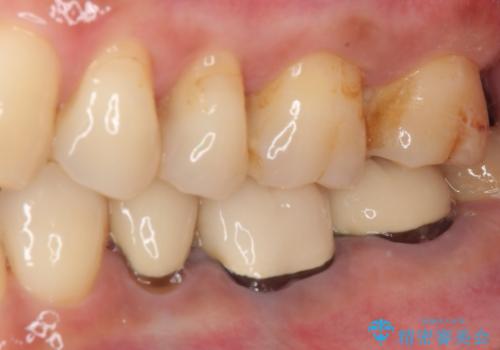

ゴールドインレーは銀歯のインレーやセラミックインレーと比べ、「技工操作の精度が高く、適合が著しく良い」というメリットがあります。特に上の奥歯は歯科医師の操作が行いにくいため、「適合の良さ」は再治療のリスクを防ぐ上でとても重要な要素となります。

上の奥歯は金属色が見えることもないため、審美的な問題は全くありません。

咬み心地はとても良好で、全く違和感がなく、患者様には大変満足していただきました。